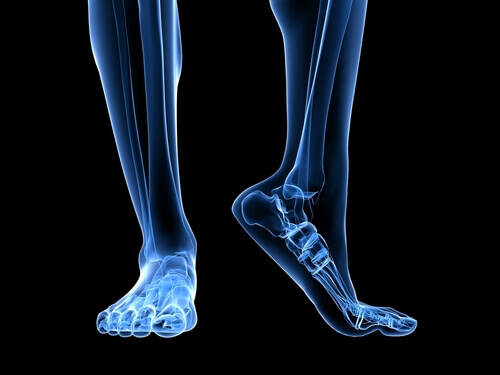

Plantar fasciitt er betennelse i plantarfascien i foten, en seneplate som knytter hælbenet med de proksimale falangene og tøyer seg og trekker seg sammen med hvert skritt, som en strikk. Plantarfascien er et veldig bredt og tykt vev på grunn av den enorme mengden press og motstand det må støtte.

Det er flere anatomiske strukturer som spiller en rolle i overbelastning av plantarfascien. Akillessenen er et ligament som forbinder gastrocnemius-musklene, kjent som leggmuskelen og flyndremuskelen (soleus), til hælbeinet. En tilbaketrekking av akillessenen utløser en økning i trykk på hælbeinet, med den resulterende økningen av presset på plantarfascien.

En annen faktor å huske på i den anatomiske strukturen er løpesteget, eller med andre ord hvordan foten berører bakken. Plattføtter eller føtter med en tendens til å overpronere strekker plantarfascien mer, og øker dermed risikoen for rifter på grunn av det ekstra trykket på vevet.